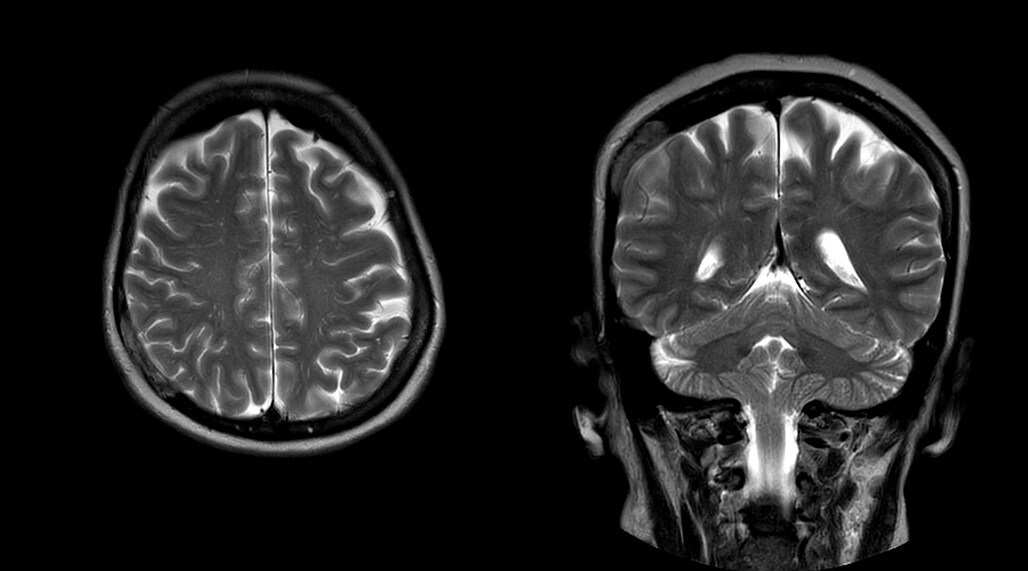

Patrick Duffy BS, RT (R) MR is Lead Technologist at DMG. “We are getting phenomenal image quality on all types of exams,” he says. “Our MSK is stellar, and so is our abdominal work. Ingenia excels at feet, hands and fingers. We do enterographies with great results. With the combination of the 3.0T magnet and the digital coils, we are able to scan prostates without an endorectal coil while still obtaining high quality results. This is a comforting experience for our male patients. We scan many obese patients, and the Ingenia does a tremendous job because of MultiTransmit, which reduces dielectric shading for more confident diagnosis. Our technologists really enjoy scanning on the Ingenia. We also have ordering physicians who specifically want their patients scanned on the Ingenia because of the results of our imaging.

“Obviously, the diagnostic capability is most important,” says Dr. Kaakaji. “Ingenia’s image quality is excellent and in follow-up studies, Ingenia provides good consistency between scans.

“Without using an endorectal coil we do our prostate MR at 0.5 mm resolution, following the European society of urology protocol [1]. For certain joints we use a virtual arthroscopy protocol with 1 mm pixel size and 2 mm slice thickness. Ingenia really excels in our neurography, brachial plexus and prostate scans. Our neurologists insist on using our 3.0T for those,” Dr. Kaakaji adds.

“The image quality is phenomenal. Robust, clear, homogenous, not obscured by dielectric shading,” adds technologist Ryan Sybesma, RT (R) MR. “Ingenia is a high performance workhorse.”

DMG recognizes MultiVane XD motion compensation is another Philips technique that contributes to image quality and scan efficiency. “We run MultiVane XD for motion-free imaging on almost all our T2-weighted brain scans, just to reduce any repeats we might get. We know our non-contrast brain scans are going to take 20 minutes almost every time,” Mr. Duffy says.

“Using MultiVane XD still allows us to turn on dS SENSE, which significantly cuts scan time compared to what we were doing before,” he adds. “We went from a 2.5 or 3-minute scan to a 1.5-minute scan with no loss in image quality. So, it not only reduces the motion, but also reduces scan time. That gives us a little bit of extra time to speak to our patients and explain the exam a little more.”